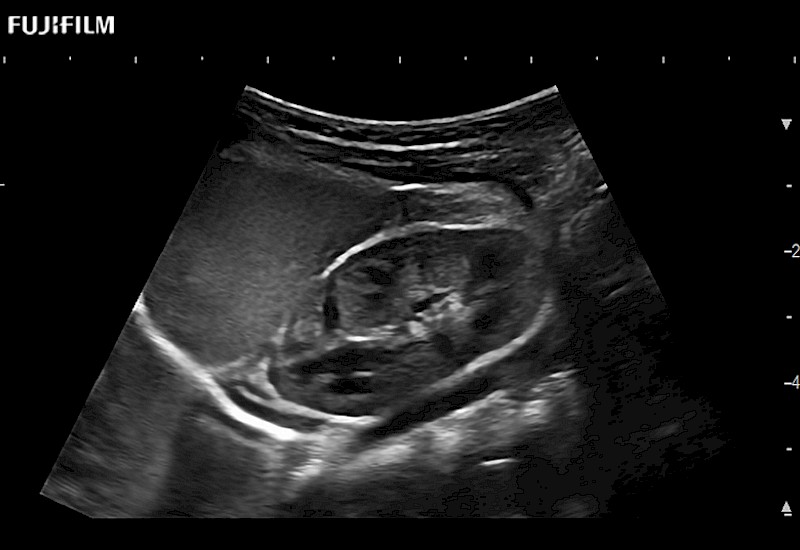

Curved array 4-way laparoscopic transducer for better visualization of targeted lesions.

Main Specifications:

Exclusive linear array 4-way laparoscopic transducer for better visualization of targeted lesions.